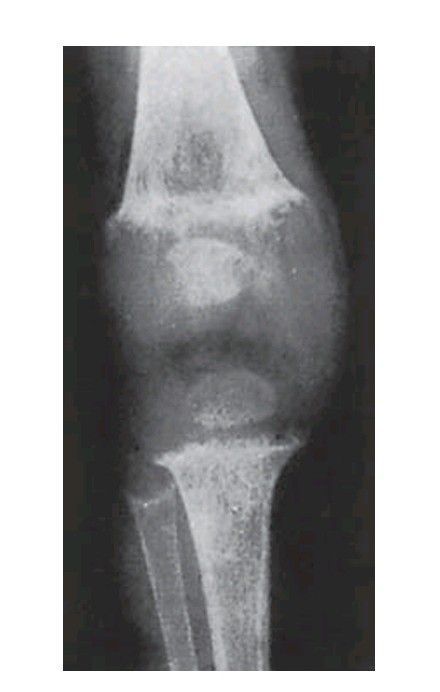

Rickets. Overgrowth of cartilage causes the epiphyseal plate to be broad, thick and irregular, and the ends of the bone become splayed. The growing end of the bone is ill-defi ned and calcifi cation defective.